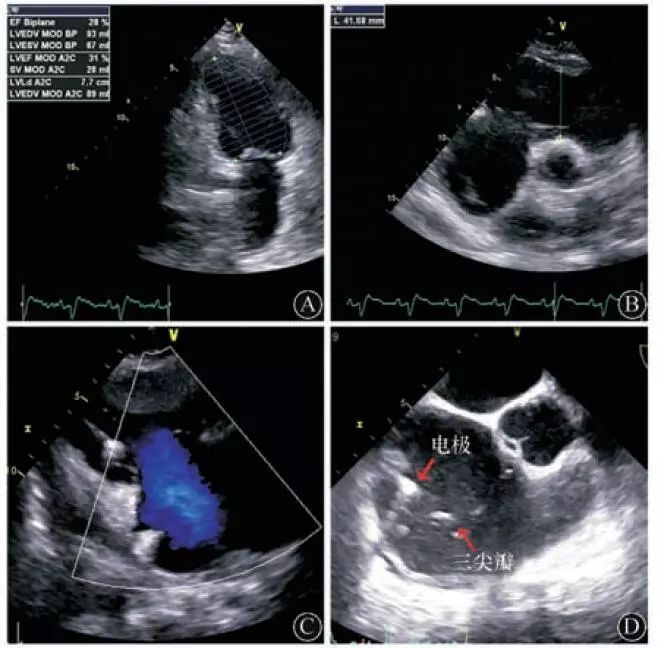

入院后查血常规:血小板83×109/L,余正常;肝肾功能:血肌酐96 μmol/L;心肌酶正常;N末端B型利钠肽原1 661 pg/ml,B型利钠肽(BNP) 360 ng/L;经胸超声心动图示全心增大,左室舒张末内径56 mm,右室横径44 mm,左、右室收缩功能减低,双平面*L法**VEF下降至28%,重度三尖瓣关闭不全(图3A,图3B,图3C),下腔静脉增宽。经食道超声心动图示重度三尖瓣关闭不全,右心内可见起搏导线回声。三尖瓣与电极间关系不易观察(图3D),未见左心耳及左右心房血栓。

经胸超声心动图:A:双平面法测LVEF为28%;B:右室流出道增宽,达到42 mm;C:三尖瓣大量反流;经食道超声心动图(D):右室电极与三尖瓣相距较远,无直接干扰三尖瓣关闭的证据

图3 患者超声心动图

总结患者多次复查的超声心动图检查结果(表1),显示患者在第二阶段主要表现为全心进行性扩大与LVEF进行性下降。首先考虑能否用原发病的"一元论"解释。典型的ARVC以右心室受累为主,表现为右房、右室扩大,右室流出道增宽以及右室收缩功能的下降,因此患者入院以后评估的右心增大可以用AVRC解释。但是ARVC亦可以累及左心,表现为双心室受累。据报道,ARVC患者双心室受累发生率达到了56%,单纯右心受累仅占ARVC病例的39%,而且还有5%的患者左心室受累比右心室更显著[2]。因此,从文献分析,一元论似乎可以解释患者整体病情发展的全貌。另一方面,患者的右心比发病初期有所扩大,三尖瓣反流量从中量增加为大量,是不是常见的起搏器心室电极对三尖瓣的干扰?因为少数植入右室电极的患者会因为电极阻碍三尖瓣关闭或者与三尖瓣叶缠绕导致三尖瓣关闭不全,造成右心增大及重度三尖瓣反流。入院以后我们重点筛查了起搏器电极与三尖瓣的关系,但是经胸超声及经食道超声均未发现上述证据。